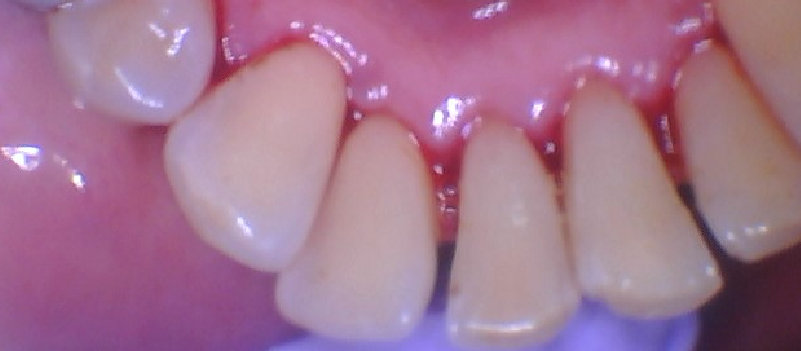

The doctor recommended a deep cleaning (scaling and root planing) to treat the infection below my gums. When they showed me before and after photos from my teeth, I was shocked! The difference was incredible—I couldn’t believe how much healthier the gums looked after treatment. It opened my eyes.

After